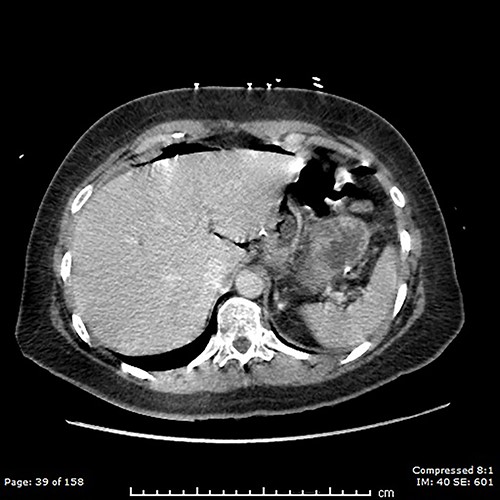

A computed tomography (CT) scan of the abdomen and pelvis showed moderate volume free gas without a clear source (Fig. 1). At diagnostic laparoscopy, there was four-quadrant purulent peritonitis and a 5-mm anterior perforation in the alimentary limb located ~15 cm from the gastrojejunostomy (Fig. 2). This was repaired laparoscopically with primary closure after excision of the ulcer edges; the histology revealed no malignancy nor Helicobacter pylori. The patient had an uneventful recovery and was discharged on post-operative day 5.